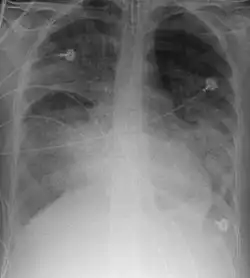

A chest X-ray showing right sided (seen on the left of the picture) pulmonary contusion associated with rib fractures and subcutaneous emphysema

Chest X-ray is the most common method used for diagnosis,[42] and may be used to confirm a diagnosis already made using clinical signs.[23] Consolidated areas appear white on an X-ray film.[47] Contusion is not typically restricted by the anatomical boundaries of the lobes or segments of the lung.[31][48][49] The X-ray appearance of pulmonary contusion is similar to that of aspiration,[36] and the presence of hemothorax or pneumothorax may obscure the contusion on a radiograph.[29] Signs of contusion that progress after 48 hours post-injury are likely to be actually due to aspiration, pneumonia, or ARDS.[13]

Although chest radiography is an important part of the diagnosis, it is often not sensitive enough to detect the condition early after the injury.[40] In a third of cases, pulmonary contusion is not visible on the first chest radiograph performed.[10] It takes an average of six hours for the characteristic white regions to show up on a chest X-ray, and the contusion may not become apparent for 48 hours.[10][31][48] When a pulmonary contusion is apparent in an X-ray, it suggests that the trauma to the chest was severe and that a CT scan might reveal other injuries that were missed with X-ray.[2]